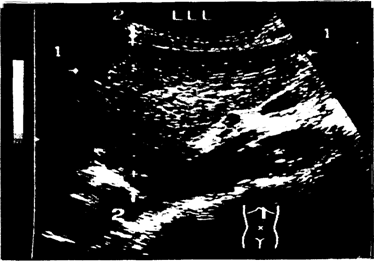

Соответствующее изображение для измерения КВР правой доли печени получается в положении косого сканирования с расположением датчика по среднеключичной линии вдоль реберной дуги с некоторым, часто индивидуально подбираемым, углом наклона в интервале от 75 до 30 °. Измерять этот размер можно практически в любой фазе дыхательного цикла, однако, в фазу максимального задержанного вдоха может быть допущена ошибка измерения, связанная с движением нижнего края печени вниз, что приведет к ложному уменьшению размера. При отсутствии патологии КВР правой доли печени не превышает 150 мм (рис. 5). Кранио-каудальный размер левой доли (ККР) соответствует величине левой доли от ее нижнего края до диафрагмальной поверхности и в клинической практике в какой-то степени соответствует одному из размеров печени по Курлову, определяемому методом перкуссии. Его нормальные показатели не превышают 100 мм (рис. 6). Толщина левой доли соответствует величине левой доли от ее передней до задней, обращенной к позвоночному столбу, поверхности.

Рис. 5. Изображение правой доли печени при измерении косого вертикального размера в положении косого сканирования вдоль правой рёберной дуги при умеренном наклоне датчика –5(f–75)°. Стрелками и маркерами отмечена ось измерения

Рис. 6. Изображение левой доли печени при измерении кранио-каудального размера и толщины левой доли в положении продольного сканирования вдоль левой парастернальной линии при вертикальном расположении датчика. Стрелками и маркерами отмечены оси измерения: 1-1 –кранио-каудальный размер, 2-2 – толщина левой доли